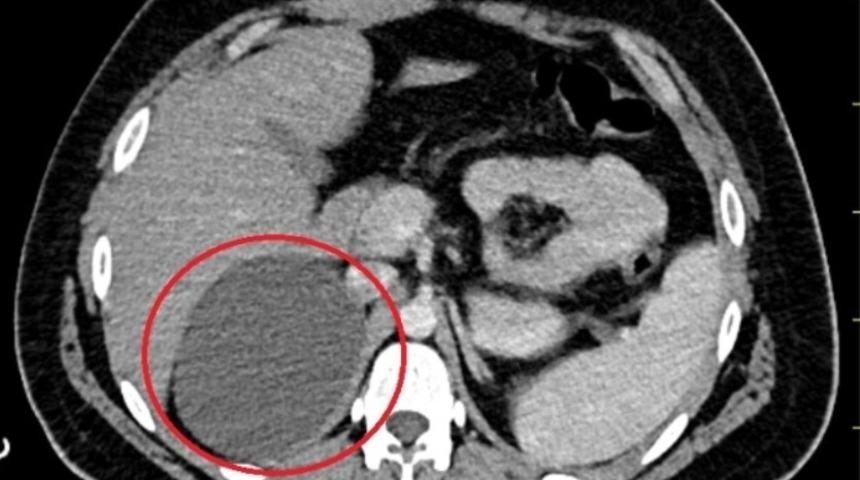

Böbreküstü bezinin üzerinde 11 santimetrelik kitle olduğu anlaşılan bir hasta, laparoskopik yöntemle ameliyat edildi. Sol böbreküstü bezinde bulunan kitlenin çıkarılmasının ardından 1 gün sonra taburcu edildi.

Eskişehir'de Üroloji Bölümü’ne bir erkek hasta böbreküstü bezindeki kitle nedeniyle başvurdu. Hastanın sol böbreküstü bezinde bulunan kitlesinin hormonal açıdan aktif olmadığı ve büyümekte olduğu tespit edildi. Kitlenin 11 santimetreye kadar ulaşması sonucu, kanser riski oluşturduğu için hastanın ameliyata alınmasına karar verildi. Üroloji Uzm. Dr. Aykut Aykaç ve Uzm. Dr. Coşkun Kaya tarafından laparoskopik yöntemle hastanın böbreküstü bezindeki kitle çıkarıldı. Eskişehir Şehir Hastanesi Üroloji Bölümü’nde ilk kez laparoskopik yöntemle gerçekleştirilen operasyonla hasta sağlığına kavuştu. Laparoskopik cerrahi ile deri üzerinden küçük bir kesi açılarak yapılan ameliyat sayesinde hasta 1 gün sonra taburcu edildi.

“Kliniğimize 18 yaşındaki erkek hasta, sağ böbreküstü bezinde kitle nedeniyle başvurdu. Kitlesi daha önceden takip altındaymış, bunun boyutu 11 santimetreye kadar büyümüş. Endokrinoloji Bölümü mevcut kitlenin hormonal olarak aktif olmadığını saptadı. Bu tarz kitlelerde hormonal olarak aktif olup olmaması önem arz ediyor. Genelde böbreküstü bezlerde kitle takibi sınırımız 4 santimetreye kadar. Kitlenin boyutu arttıkça da kanser çıkma ihtimali arttığı için cerrahi müdahale söz konusu oluyor. Laparoskopik cerrahinin avantajı küçük bir kesi açarak ameliyatı yapıyoruz. Yaranın iyileşmesi daha çabuk ve kan kaybı daha az oluyor. Hasta daha erken günlük yaşantısına dönüyor. Biz bu ameliyatı laparoskopik olarak gerçekleştirdik. Hastanın dreninden de kan gelmediği için de taburcu ettik. Hastanemizde ilk kez alanımızda bu ameliyatı laparoskopik yöntemle gerçekleştirdik.”